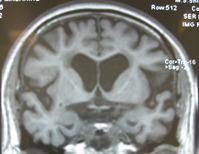

高次脳機能検査で認知障害が疑われた場合に、脳MRI検査など画像診断で原因を調べます。認知症の原因として最も多いアルツハイマー型認知症では、下の脳MRI画像のように記憶に関わる側頭葉内側の海馬の萎縮が見られます。初期のアルツハイマー型認知症では、海馬萎縮は軽度で、判定が難しいのですが、当院ではこれを定量的に診断するソフトウエア(VSRAD)を利用して、より確実な診断が可能になっています。